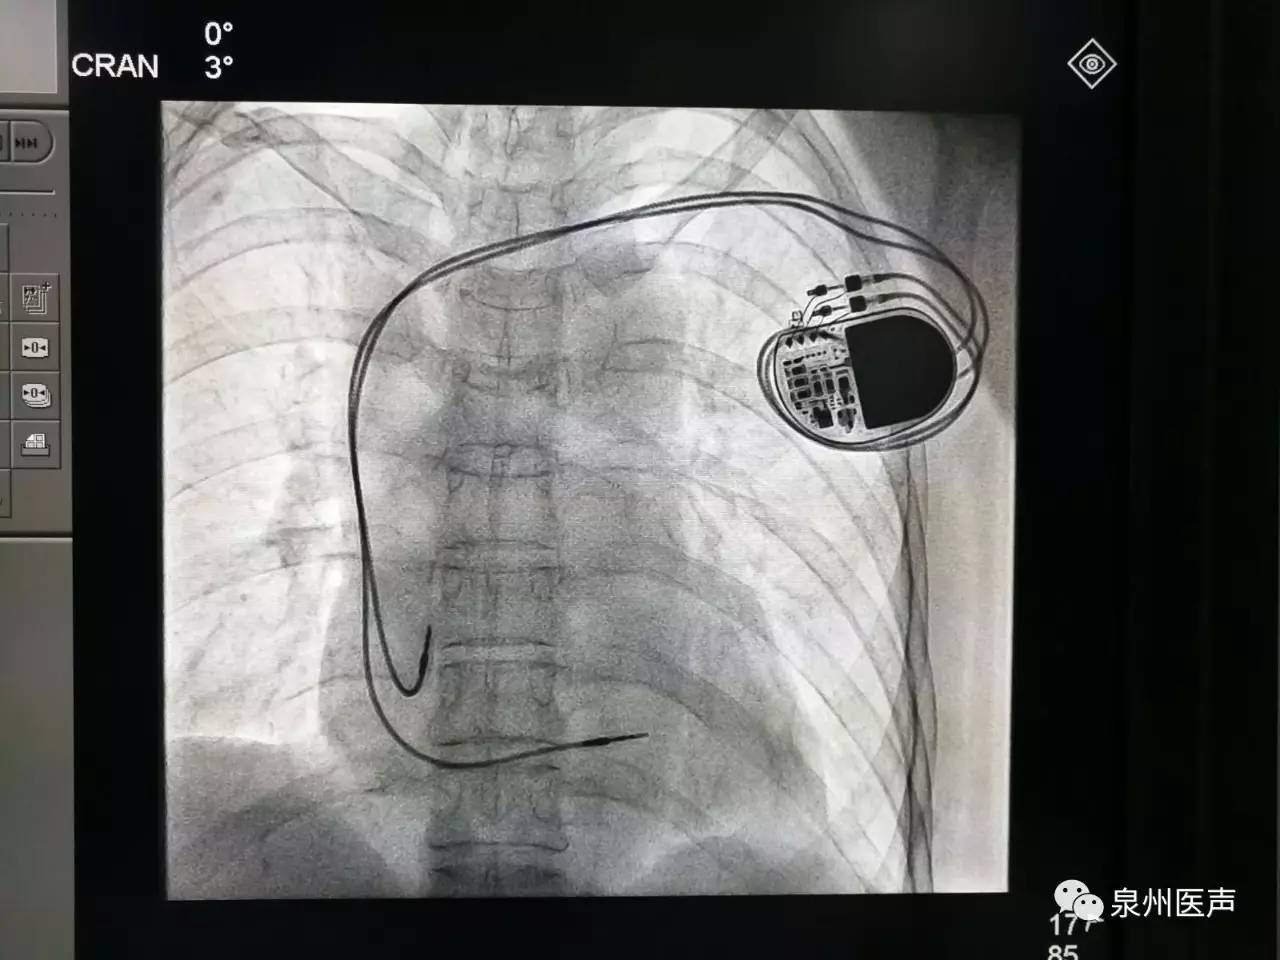

微創(chuàng)、樂(lè)普、先健填補(bǔ)國(guó)產(chǎn)起搏器市場(chǎng)空白,釋放哪些信號(hào)?

世界最小起搏器,正式進(jìn)入中國(guó)市場(chǎng)!